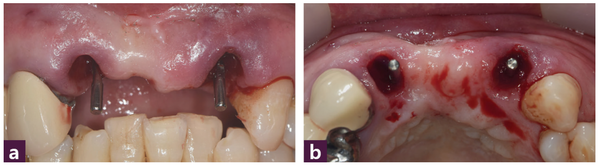

59세 남성 환자로 12번-22번 부위 4-unit bridge의 동요도로 내원했다. 식립 전 구강 내 사진에서 12번과 22번 치아의 치은 퇴측(gingival recession)이 관찰됐다 [그림 2].

Case 1은 [그림 2a]에서 보는 바와 같이 중등도 이상의 치주질환으로 인해 gingival recession이 동반된 상태인 가장 어려운 임상 case 중 하나이다. 왜냐하면 치은의 양과 높이, 그리고 골 양과 골 높이 모두 부족한 상태이므로 임플란트 식립에 성공하더라도 연조직 상태를 개선하지 못한다면 치료에 실패할 수 있기 때문이다. 치료계획으로 4개월 이후의 지연 식립은 골소실이 현재의 상태보다 많아질 것으로 판단해 배제했고 발치 후 즉시 식립 또는 4~6주 후의 연조직 상태에 따라 식립하는 방법을 고려했으나 환자의 심미적 요구가 크지 않아서 발치 후 즉시 식립을 선택했다.